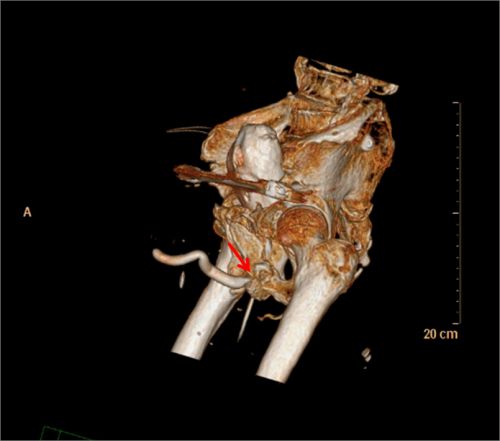

三维ct成像显示膀胱尿道的立体结构、与直肠的关系,以及骨盆的稳定性和恢复情况。

入院后,经过膀胱尿道造影X线检查发现后尿道闭锁的部位和长度,了解了患者尿道损伤部位没有假道、瘘管发生;骨盆和膀胱尿道三维CT成像显示膀胱尿道的立体结构、与直肠的关系,以及骨盆的稳定性和骨折的恢复情况。